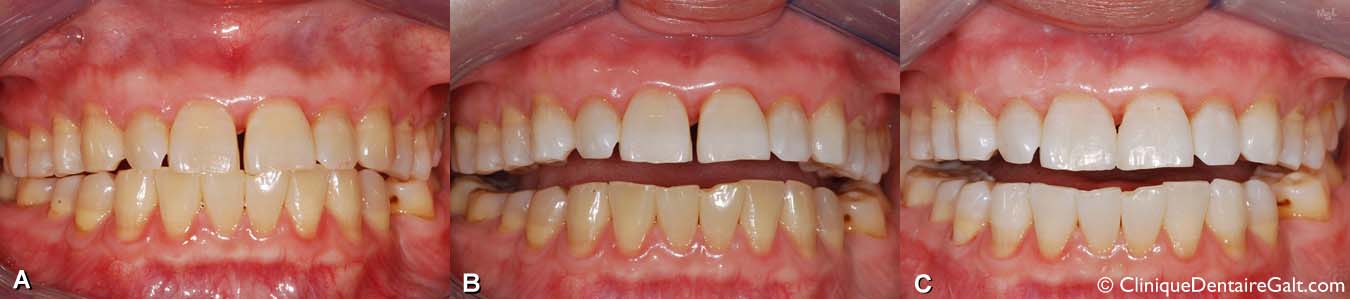

Exemple de blanchiment dentaire fait par le patient à la maison avec des coquilles de blanchiment fabriquées par son dentiste.

(A) Avant le traitement.

(B) Après le blanchiment de l’arcade supérieure.

(C) Après le blanchiment de l’arcade inférieure. Du composite dentaire a été ajouté entre les incisives centrales supérieures pour fermer un léger diastème. Il est important de faire le blanchiment AVANT que des dents soient restaurées avec un matériau esthétique pour avoir une couleur uniforme. Si le composite était posé avant le blanchiment, sa couleur aurait pu être différente de celle de l’émail dentaire une fois le blanchiment terminé.